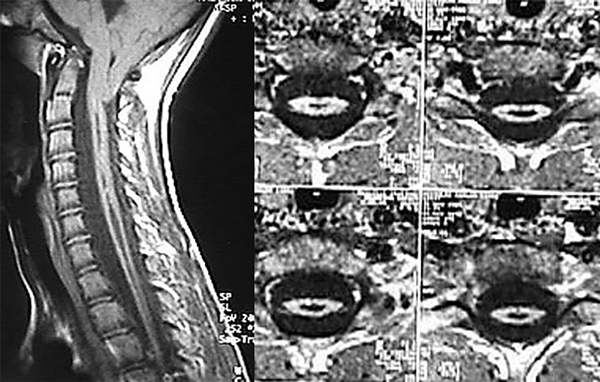

Paciente masculino de 4 años y 6 meses con ausencia de reflejos cutáneos abdominales y una escoliosis torácica de convexidad izquierda, cuyo valor angular de Cobb T-L3 de 230° y convexidad izquierda se trató con corsé toraco-lumbosacro (tipo TLSO). La RM mostró una malformación de Chiari tipo I asociada a una extensa siringomielia, desde C2 a T9 (Figura 1). Los potenciales evocados somatosensoriales (PESS) resultaron normales. Se adoptó conducta expectante.

Figura 1. Cortes sagital y axiales en los que se observa extensa dilatación siringomiélica. Espinograma, frente.